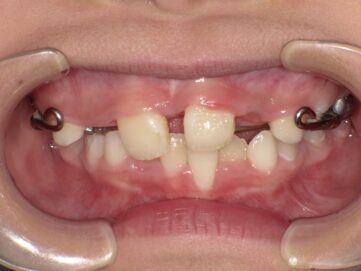

上顎の骨には繋ぎ目が存在しており、そこで左右二つの骨に分かれています。急速拡大装置を上顎に固定して装置の中央にあるネジを回すことで繋ぎ目を広げ、徐々に上顎の骨の変えていきます。そうすることで、顎の骨が正しい形に成長していくよう促され、永久歯を正しい位置で生えるように誘導できます。

急速拡大装置で上顎の拡大が進むと、下顎の骨も調整する必要が出てきます。その際に使う装置がリンガルアーチです。下顎の骨は上顎の骨と作りが違います。下顎はひとつの骨で構成されているので、上顎と同じように拡大させることができません。内側に傾いている歯を起こすようにして歯列部分だけを拡げていきます。この装置も固定式の装置となっており、歯の裏側に装着しますので目立たない見た目となっています。

上顎の拡大と下顎の歯の調整が進むと、機能的矯正装置であるアクチバトール(FKO)という装置を使用します。アクチバトール(FKO)は着脱式の矯正装置で、下顎を適切な位置へ誘導します。 顎の位置、形態が改善し、舌、口唇の位置、使い方が改善すれば、自然に歯の位置が変わって歯が綺麗に並ぶようになります。